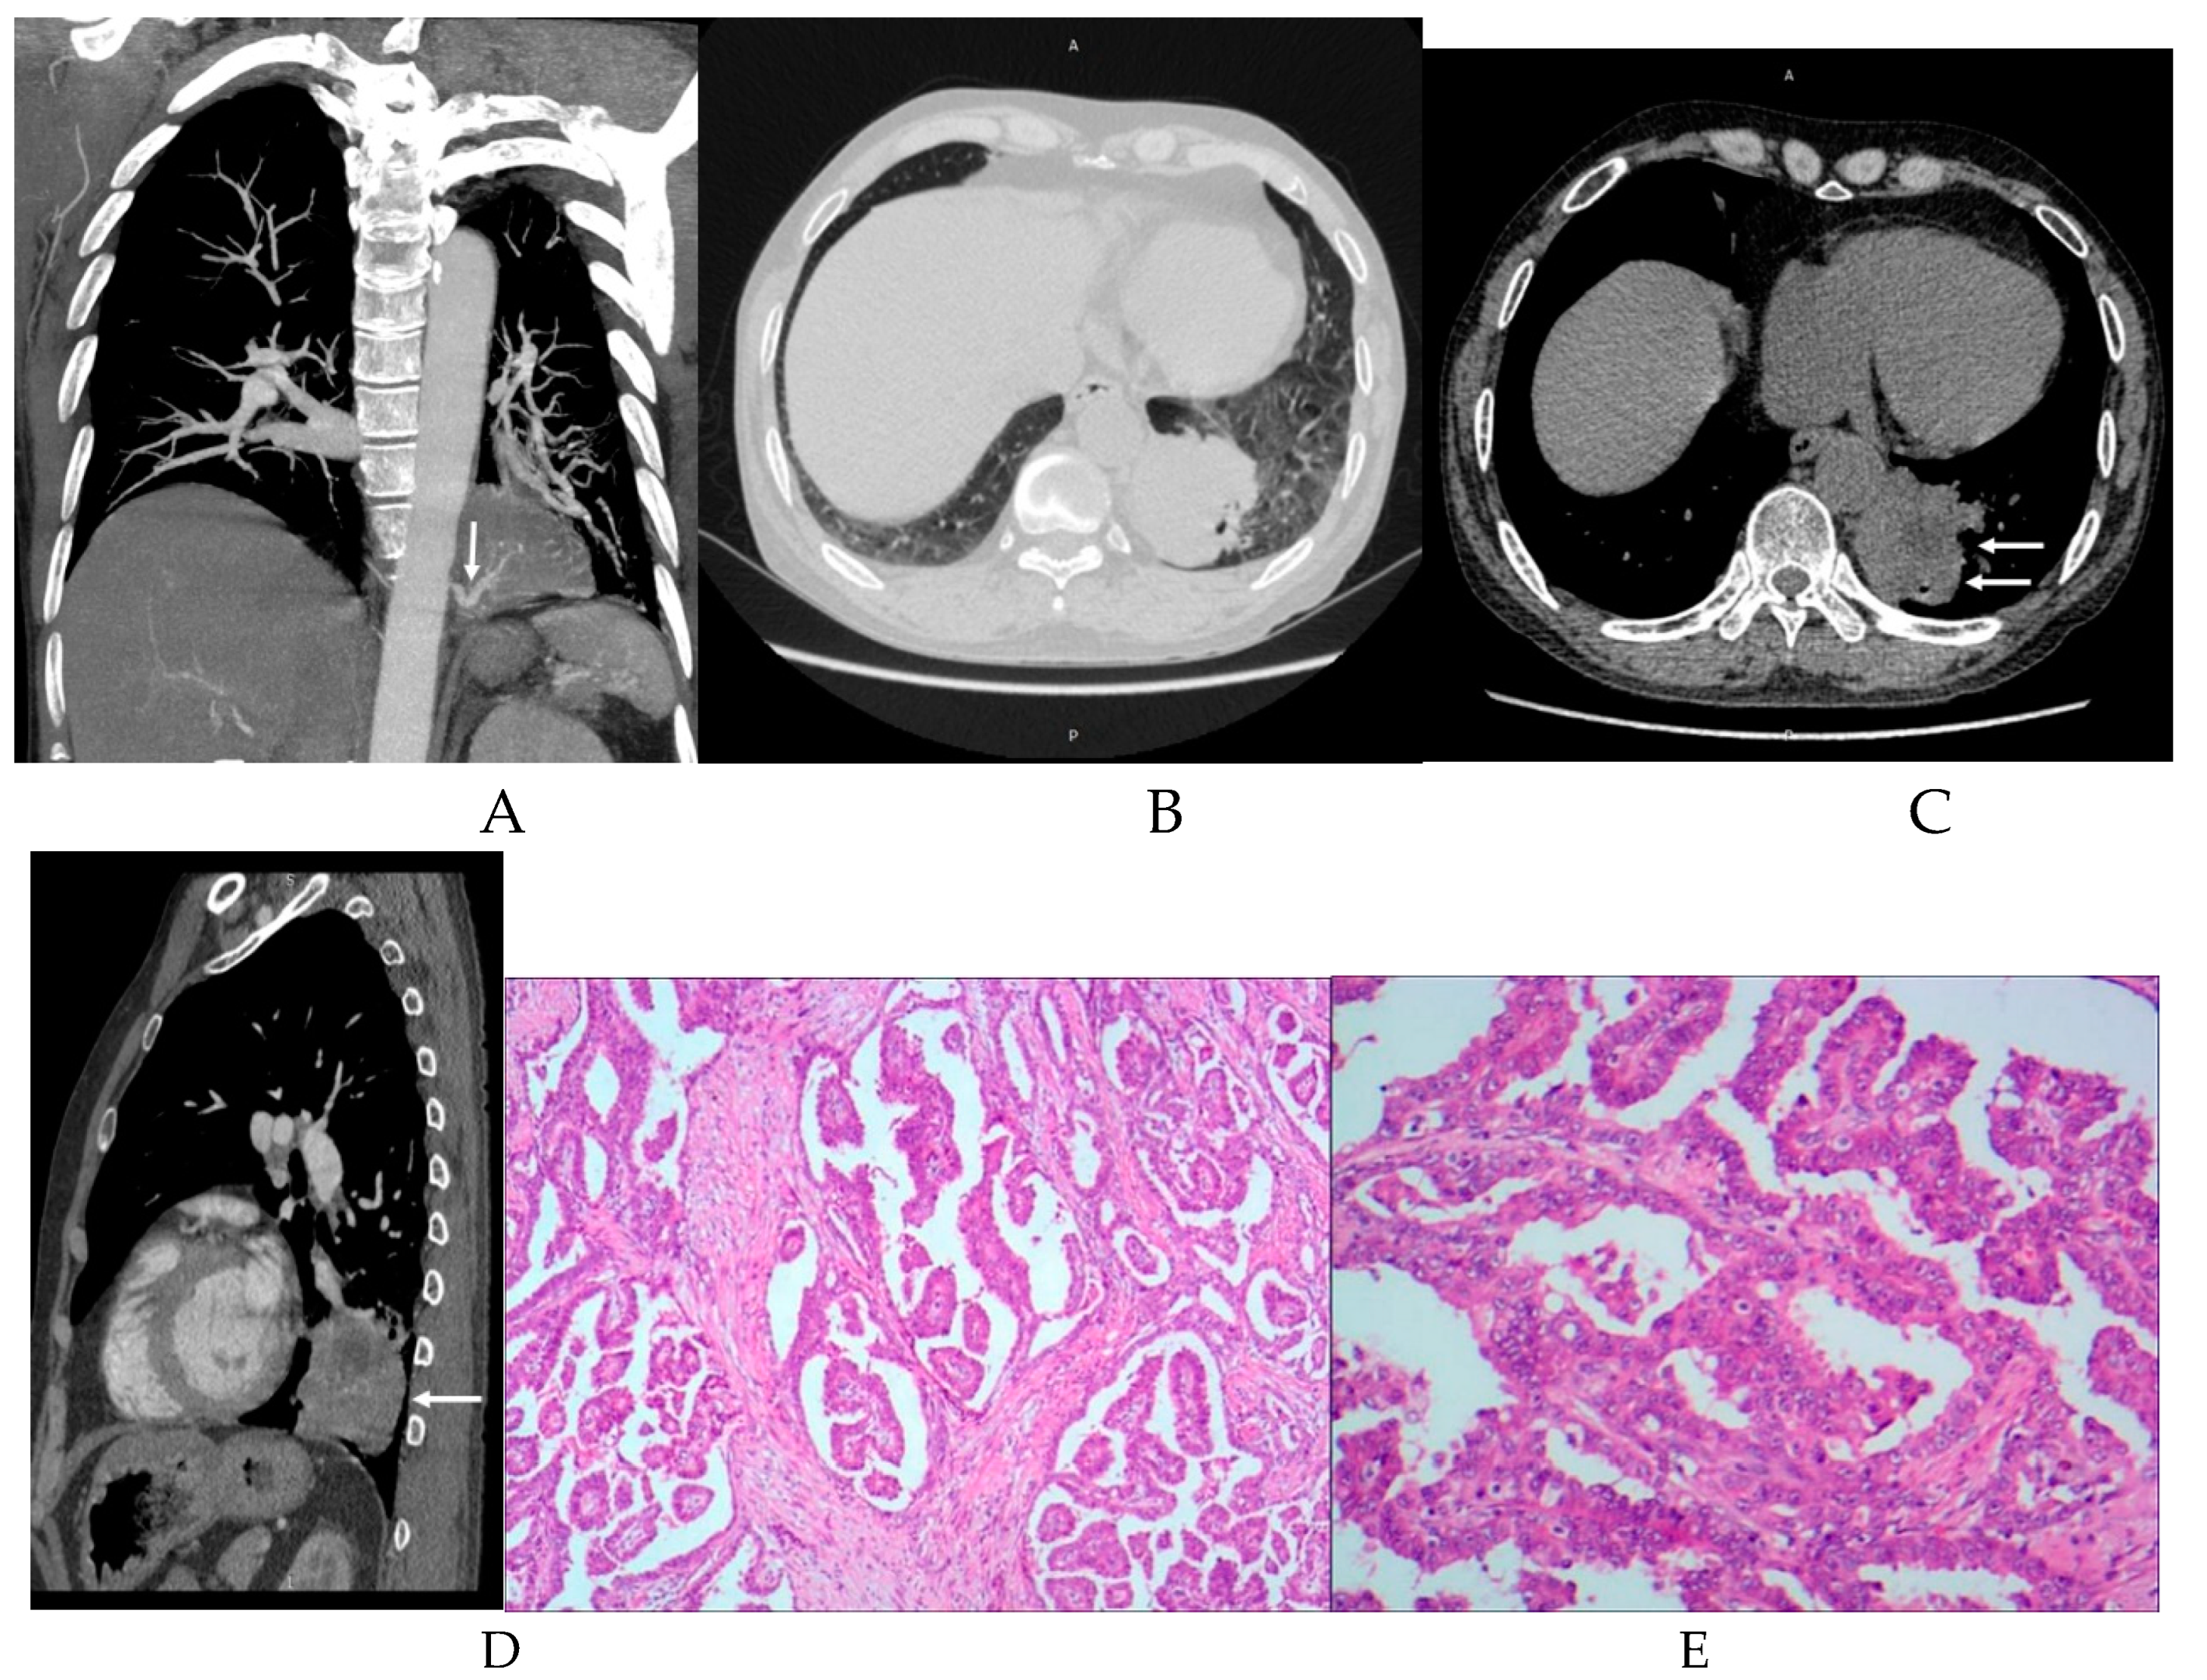

3.2. Imaging appearances of CTPA

| Imaging appearances | Subtype | Number of cases |

| Subtype of disease | ILS | 54(98.18%) |

| ELS | 1(1.82%) | |

| Location of disease | LLL | 42(76.36%) |

| RLL | 12(21.82%) | |

| BLL | 1(1.82%) | |

| Supplying artery | Aorta A | 1(1.82%) |

| Aorta D | 47(85.45%) | |

| CA | 7(12.73%) | |

| BA | 1(1.82%) | |

| Draining vessels | PV | 49(89.09%) |

| UV | 1(1.82%) | |

| IV | 1(1.82%) | |

| PA | 11(20.00%) | |

| NF | 2(3.64%) |